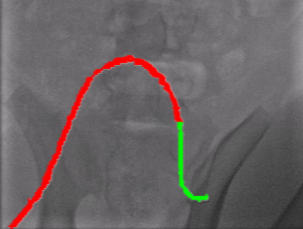

Qualitative Results. Fig. 5 illustrates the catheter and guidewire segmentation results of fine-tuning ViT on our method and different foundation models. The visualization portrays that our method excels in accurately delineating the catheter and guidewire structures, showcasing superior segmentation performance compared to other approaches. This figure further confirms that we can successfully train a federated endovascular foundation model without collecting users’ data and the trained foundation model is useful for the downstream segmentation task.

|

Animal |

Phantom |

Simulation |

Input

Ground Truth

LVM-Med

SAM

CLIP

Ours